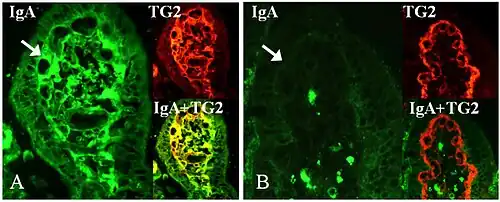

Tissue transglutaminase

Tissue transglutaminase modifies gluten peptides into a form that may stimulate the immune system more effectively.[43] These peptides are modified by tTG in two ways, deamidation or transamidation.[44]

Deamidation is the reaction by which a glutamate residue is formed by cleavage of the epsilon-amino group of a glutamine side chain.[45] Transamidation is the cross-linking of a glutamine residue from the gliadin peptide to a lysine residue of tTg in a reaction that is catalysed by the transglutaminase.[44] Crosslinking may occur either within or outside the active site of the enzyme. The latter case yields a permanently covalently linked complex between the gliadin and the tTg. This results in the formation of new epitopes believed to trigger the primary immune response by which the autoantibodies against tTg develop.[46]

Stored biopsies from people with suspected coeliac disease have revealed that autoantibody deposits in the subclinical coeliacs are detected prior to clinical disease.[43]